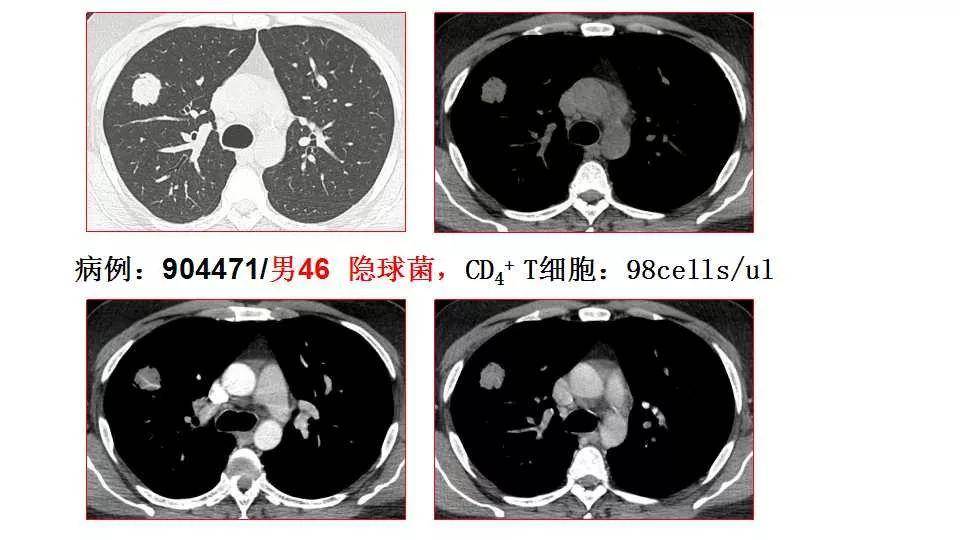

小结: 单发结节型与肺肿瘤鉴别的确存在难度 类似于免疫正常人群 a